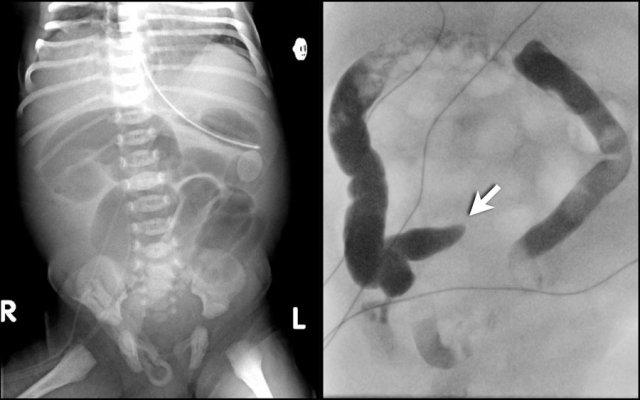

Các dấu hiệu bao gồm:

- Nhiều quai ruột non giãn cho thấy tắc nghẽn đoạn thấp

- Thụt tháo cản quang cho thấy khẩu kính trực tràng nhỏ hơn so với khẩu kính đại tràng sigma

- Trực tràng có hình ảnh co thắt dạng răng cưa.

Chẩn đoán:

Bệnh Hirschsprung đoạn ngắn.